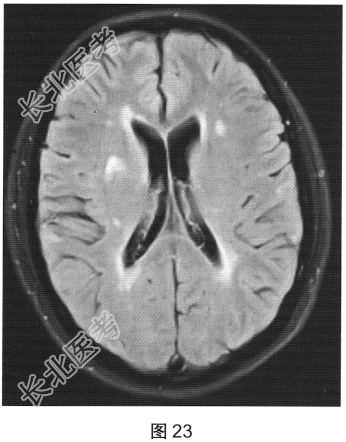

患者女性,40岁,渐进性肢体无力6个月。颅脑MRI检查如图23、图24所示。

- 多项选择题1.根据MRI表现,可能的诊断是( )

A、多发脑缺血

B、脑白质病变

C、脑白质稀疏

D、脑萎缩

E、多发性硬化

F、脑炎